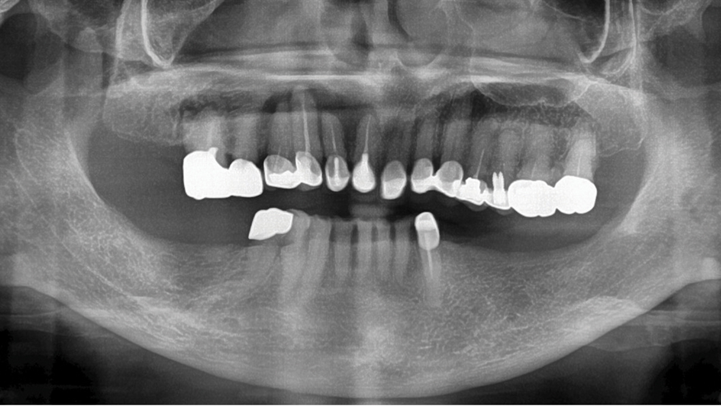

Clinical case: Ridge splitting technique using SmarThor + AnyRidge as expander

- Courtesy of Dr.Kwang-Bum Park, Korea -

Keywords

AnyRidge, ridge splitting, GBR, Dr. Kwang-Bum Park, mandibular posterior, SmartThor, Mega-Oss, thin ridge, bone regeneration

Products:

AnyRidge implant system. SmarThor, Mega-Oss

“Thin ridge expansion with minimally invasive surgery!

Use SmarThor & AnyRidge to place a wider diameter implant with minimal drilling after ridge splitting, even in thin ridge under 2mm! “